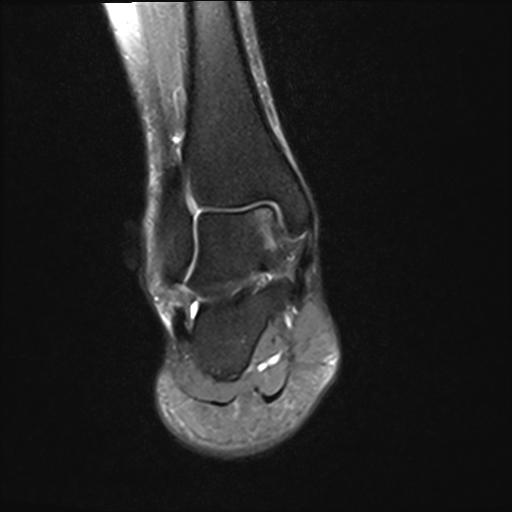

Quando Realizar a Ressonância Magnética?

A ressonância magnética (RM) é recomendada quando há suspeita de lesões mais complexas que não podem ser confirmadas apenas com exame clínico ou radiografias simples. Algumas situações em que a RM é indicada incluem:

- Persistência dos Sintomas: Se o paciente apresenta dor e inchaço persistentes após quatro a seis semanas de tratamento conservador, a RM pode ser necessária para investigar lesões ligamentares ou tendíneas mais graves.

- Suspeita de Lesão Osteocondral: Em casos de dor persistente no tornozelo após uma entorse, a RM permite identificar possíveis lesões na cartilagem ou osso subjacente.

- Instabilidade Crônica: Pacientes com histórico de entorses frequentes ou instabilidade no tornozelo podem apresentar lesões ligamentares crônicas que só são visíveis com a RM.

- Complicações Tendíneas ou Síndrome do Impacto: A RM é útil para diferenciar lesões nos tendões peroneais ou para detectar pinçamentos anteriores e posteriores no tornozelo.

Case courtesy of Vinay Shah, Radiopaedia.org. From the case rID: 20162